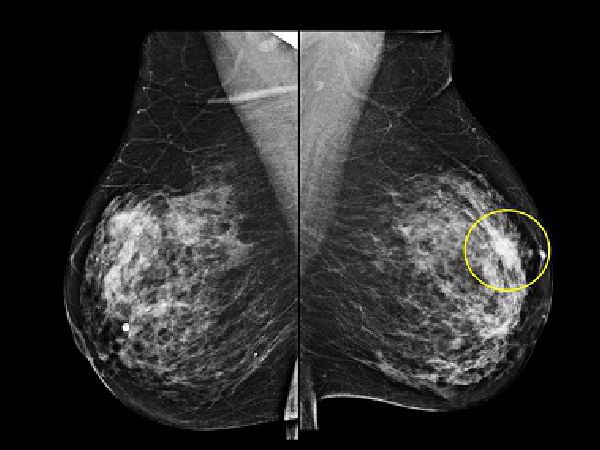

• Breast cancer treatment: Surgery in collaboration with Multidisciplinary team.

• Oncoplastic breast surgery: re-shaping of breast after excision of cancer.